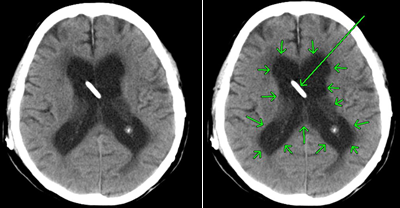

びまん性軸索損傷の具体例

症状固定段階でのT2スター強調のMRI画像です。頭頂部から頭蓋底に至る24枚のMRI画像の内の6枚目の画像です。

前頭葉、両側頭葉に黒い点がいくつか映っています。これは、脳表面の広範囲に広がる点状出血が画像として映ったものです。びまん性軸索損傷があることを示します。

点状出血を矢印で示したものが下の画像です。

被害者はフルフェイスのヘルメットを装用していました。頭蓋骨骨折や脳挫傷はありませんでした。

しかし、広範囲の点状出血に伴う軸索の損傷があります。失語、記憶、聴覚や嗅覚、言語理解、認知の領域で、脳は大部分の機能を喪失してしまいました。